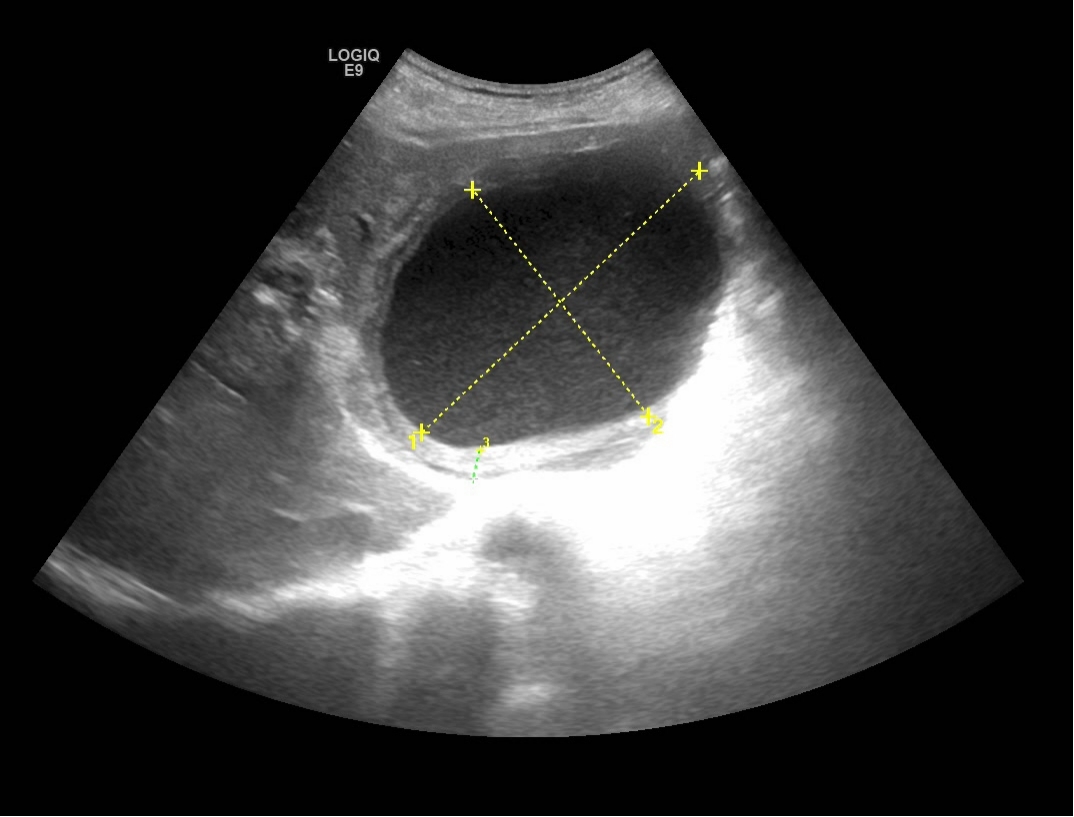

一名73岁的男性,因腹痛、发热4天,来我院消化内科就诊。经查体,患者以中上部腹痛为主,体温最高39.0℃。腹部彩超检查显示,肝左叶可探及大小约108x79mm的巨大囊性回声,挤压周围正常肝组织和血管,内部“灰蒙蒙”的。

消化内科主任张排旗与超声科主任罗利红联合会诊,考虑患者发热和肝囊肿合并感染有关,决定给予抗感染治疗的同时,行超声引导下肝囊肿合并感染穿刺置管引流术。置管后,患者发热消退,腹痛缓解,脓腔明显变小,引流出500ml脓液,并进行细菌培养,结果为大肠埃希菌。患者症状明显缓解,感染得到控制,恢复良好。